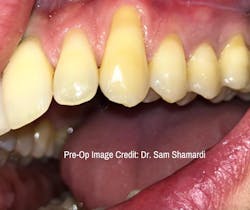

Additionally, there is an early-stage recession in adjacent teeth, but the patient only wants to treat the canine. The patient lacks a foundation of keratinized tissue and admits to being an aggressive brusher; the extent of recession is 5 mm and is down to the mucogingival junction (MGJ). Due to the primary goal being root coverage, the technique of choice is connective tissue grafting.

- The patient was concerned regarding the aesthetics of tooth no 11

- Chief concern: Lack of keratinized tissue, root exposure, mild sensitivity

- Radiographic analysis: Bone levels WNL

- Clinical analysis: Probing depths WNL, significant attachment loss, minimal keratinized tissue, sensitivity to touch, no mobility

- Etiology: Plaque and bacteria, orthodontics, aggressive brushing

- Goals of therapy: Root coverage

- Procedure chosen: Connective tissue graft